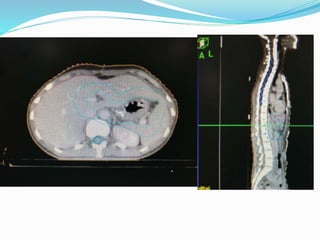

Simulation film for T3 antral tumor with two of five peritumoral lymph

nodes metastatically involved

• 51.

Simulation film forT3 antral tumor with two of five peritumoral lymph nodes metastatically involved

• 78.

Editor's Notes

• #21 In 2006 wu et al published a trial 221 pts. undergoing D1 and D2 resection with curative intent.

• #52 Simulation film for T3 antral tumor with two of five peritumoral lymph nodes metastatically involved (radical subtotal gastrectomy with D1 node dissection). Simulation film identifies areas at risk for recurrence, including preoperative gastric/tumor bed (defined by preoperative computed tomography [CT] scan), anastomotic sites and gastric stump (staple line seen on precontrast simulation films and marked on postintravenous pyelogram/postcontrast film), and regional lymphatics (celiac, porta hepatis, superior mesenteric artery, and splenic nodes identified on CT, and pancreaticoduodenal nodes lie in C-loop of duodenum identified by preoperative CT). The right kidney is spared for approximately three-fourths of its volume, whereas the left kidney has about one-third of its volume blocked